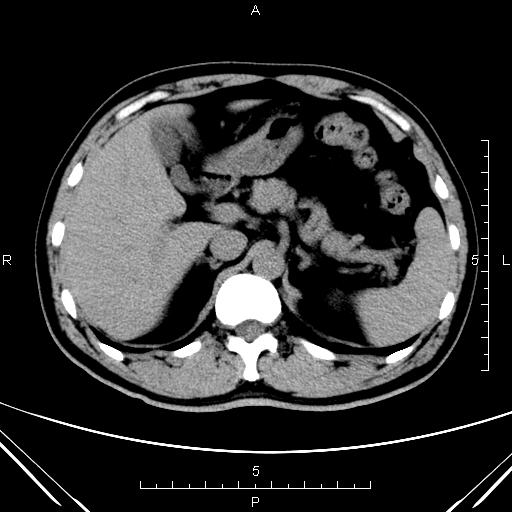

CT51137:肾脏CT

男,58岁,体检彩超示:1 右肾囊肿 2 右肾上极低回声结节(略向外突出,直径约1.6cm)。

1)右肾多发性囊肿。2)腹主动脉钙化。

右肾内可见多个类圆形不强化低密度影,考虑右肾多发性囊肿可能性大。